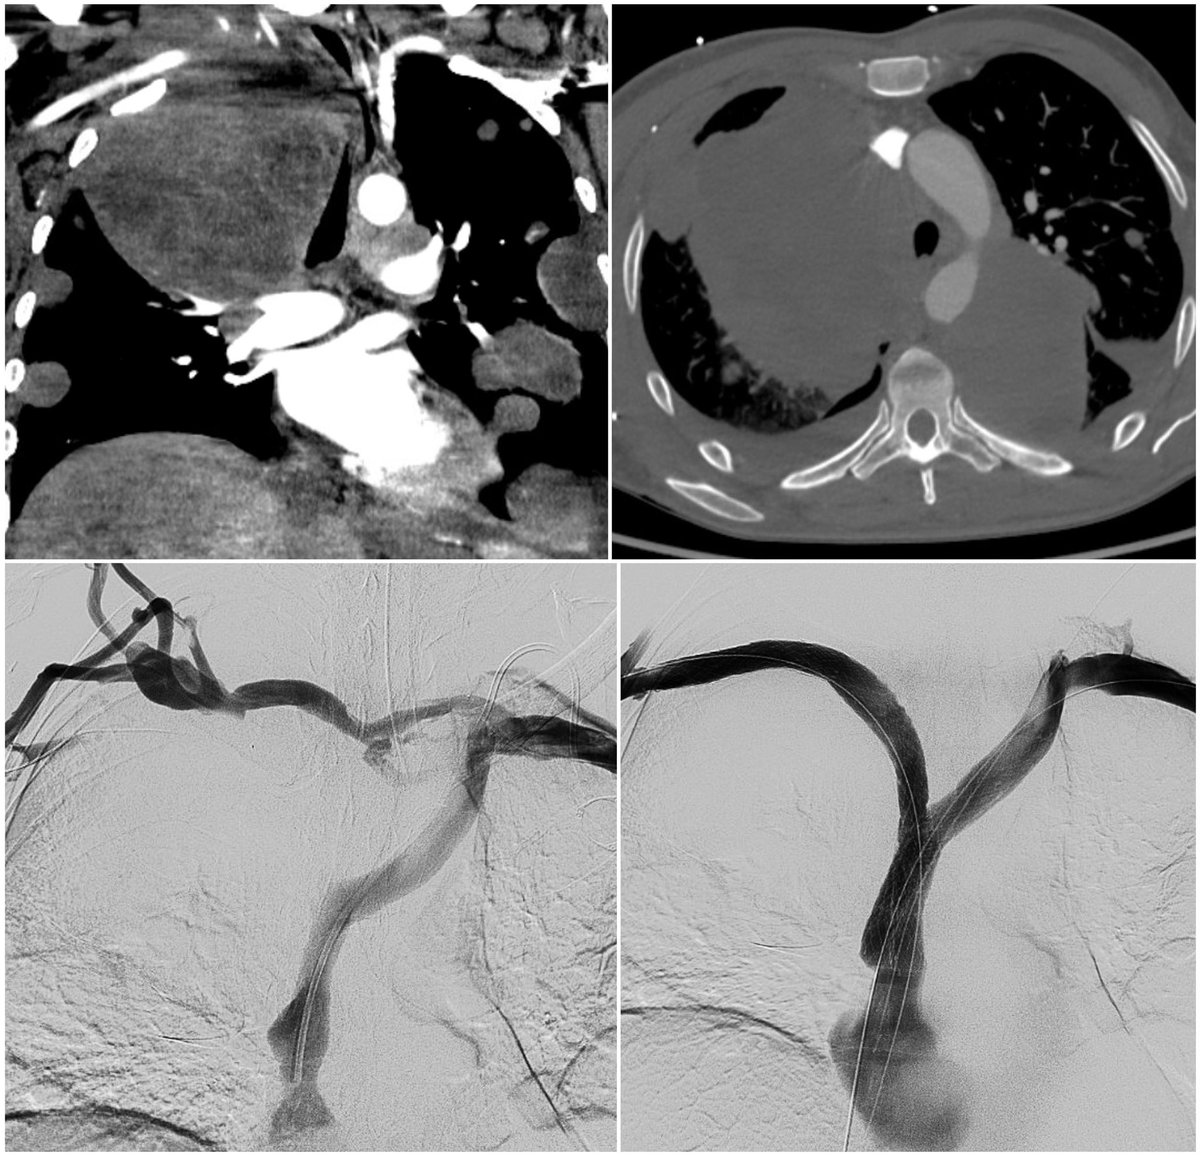

Grade IV splenic laceration in a hemodynamically-stable patient referred to international radiology for splenic artery embolization. This #IRad procedure reduces the pressure on the injured spleen, preserves flow via collateral vessels, & improves splenic salvage in #trauma.